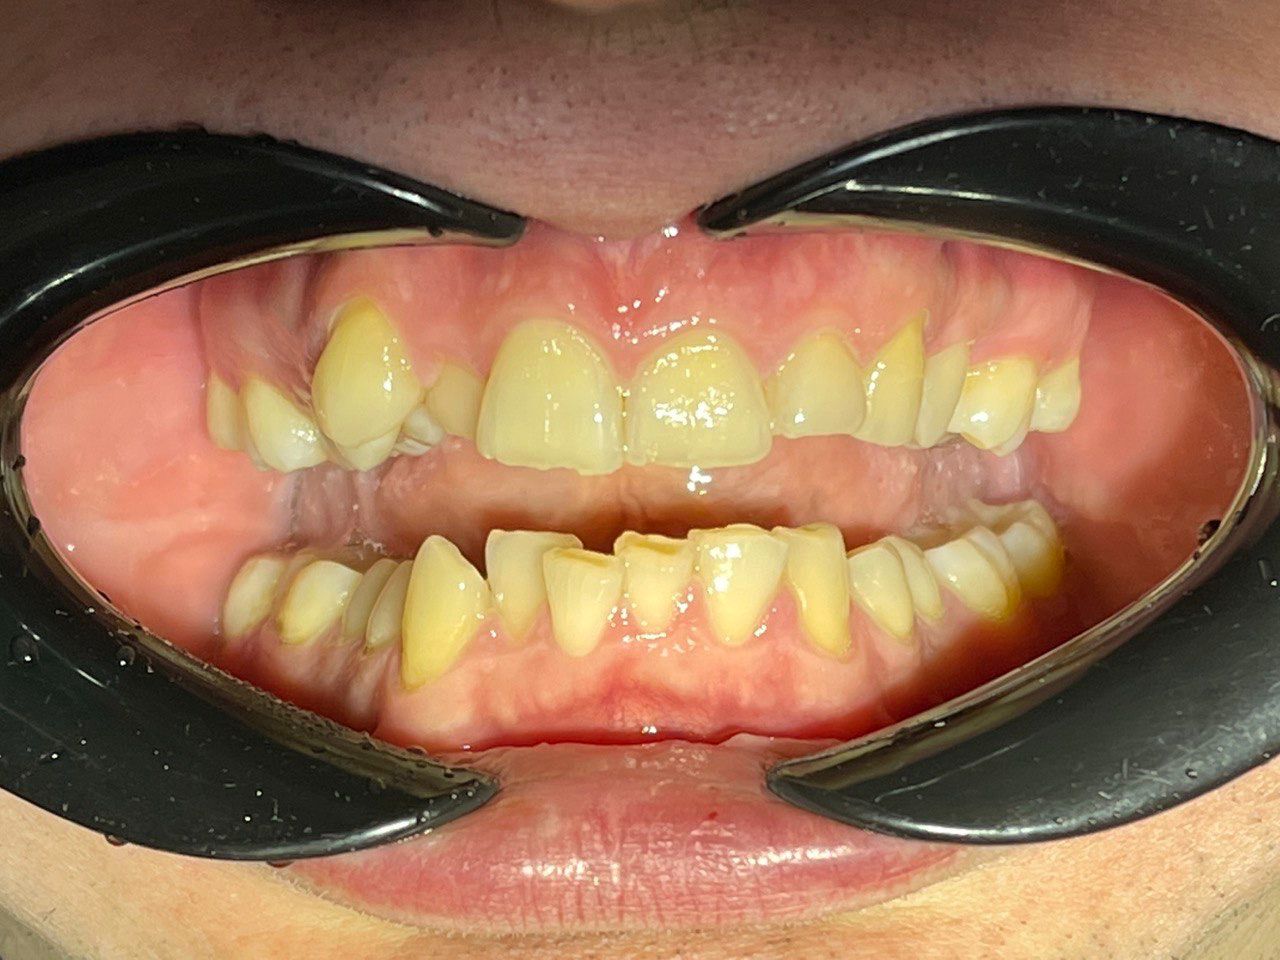

Выявленные проблемы

• Глубокое резцовое перекрытие

• Сужение верхнего и нижнего зубных рядов

• 23 зуб в щёчном положении, 22 зуб в нёбном положении с дефицитом места

• Скученное положение зубов дистальное положение и ротация нижней челюсти

• Патологическая стираемость и генерализованный пародонтит с рецессией десневого края

Брекет-система Q